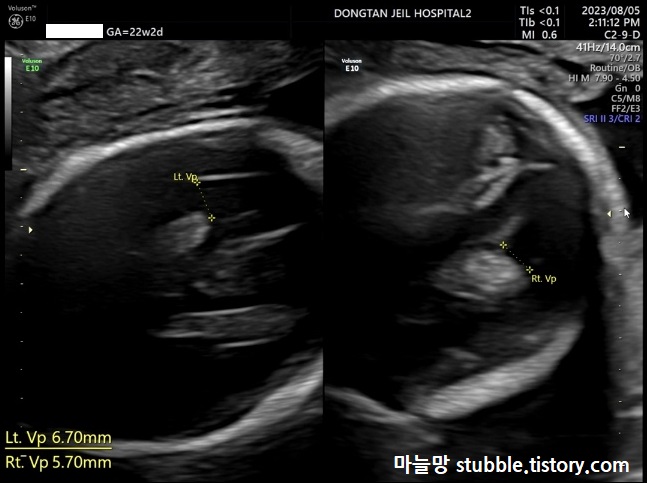

10. 뇌실크기 (Lt VP / Rt VP)

뇌실이라는 것은 뇌 안에 존재하는 4개의 서로 연결된 빈 공간을 일컫는 용어라고 합니다. 뇌척수액이 뇌실 안에서 생산되어 순환하며 채우고 있다라고 정의되어 있습니다.

뇌실 크기를 잽니다.